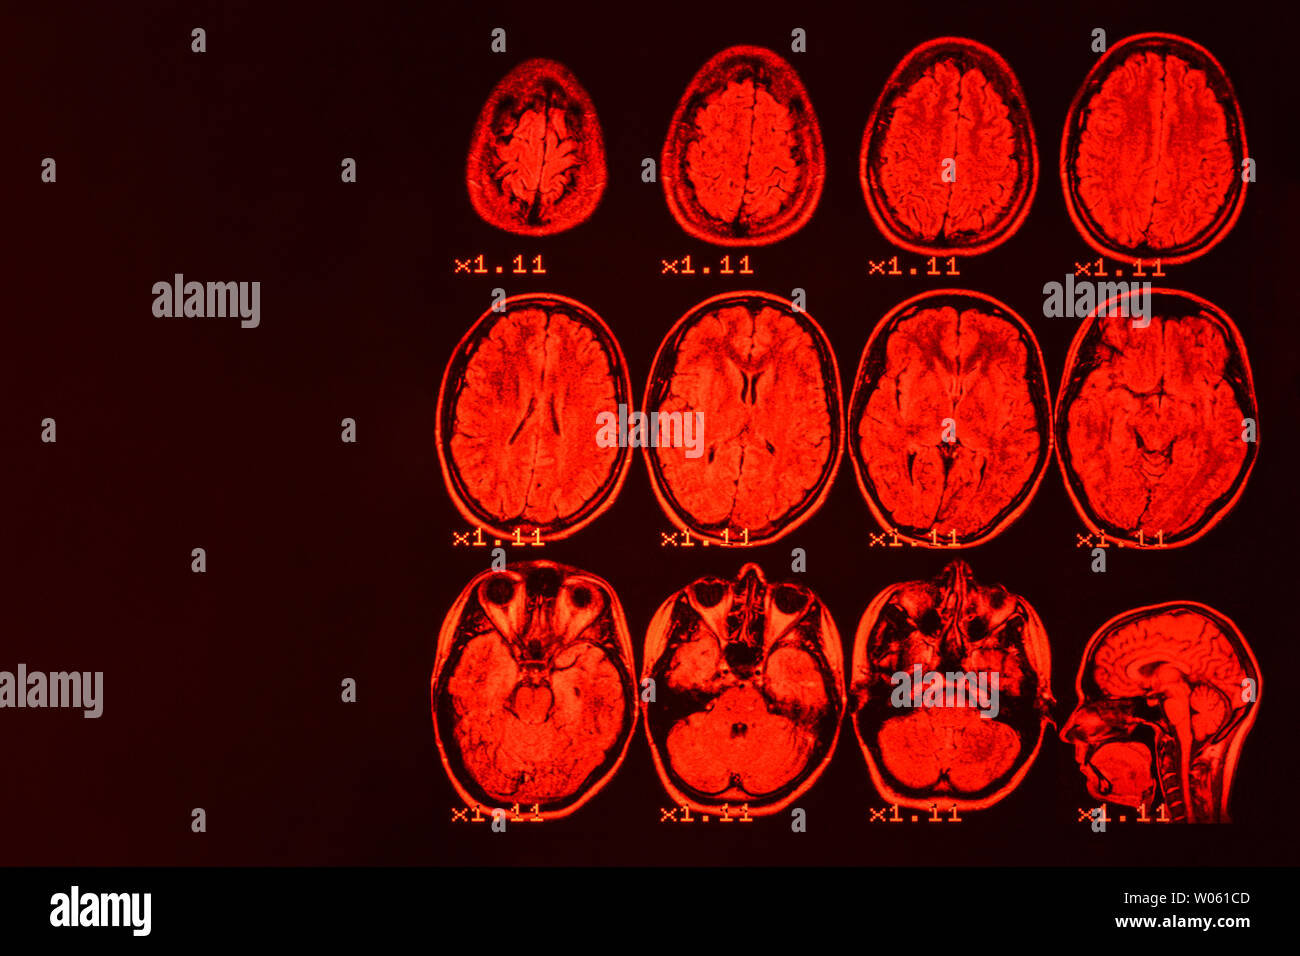

MRI of the brain on a black background with red backlight. Medical background Stock Photohttps://www.alamy.com/image-license-details/?v=1https://www.alamy.com/mri-of-the-brain-on-a-black-background-with-red-backlight-medical-background-image258288365.html

MRI of the brain on a black background with red backlight. Medical background Stock Photohttps://www.alamy.com/image-license-details/?v=1https://www.alamy.com/mri-of-the-brain-on-a-black-background-with-red-backlight-medical-background-image258288365.htmlRFW061CD–MRI of the brain on a black background with red backlight. Medical background